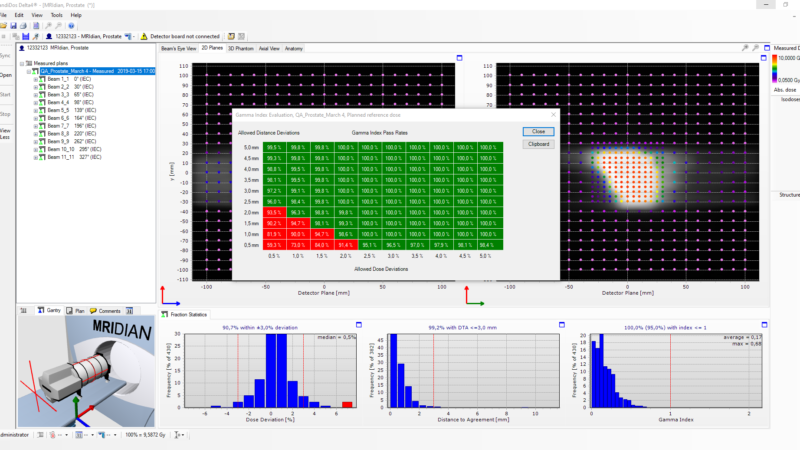

Delta4 software

Streamline your workflow

Delta4 software

Instant and accurate analysis

- Instant results in one place

- Powerful analytic tools